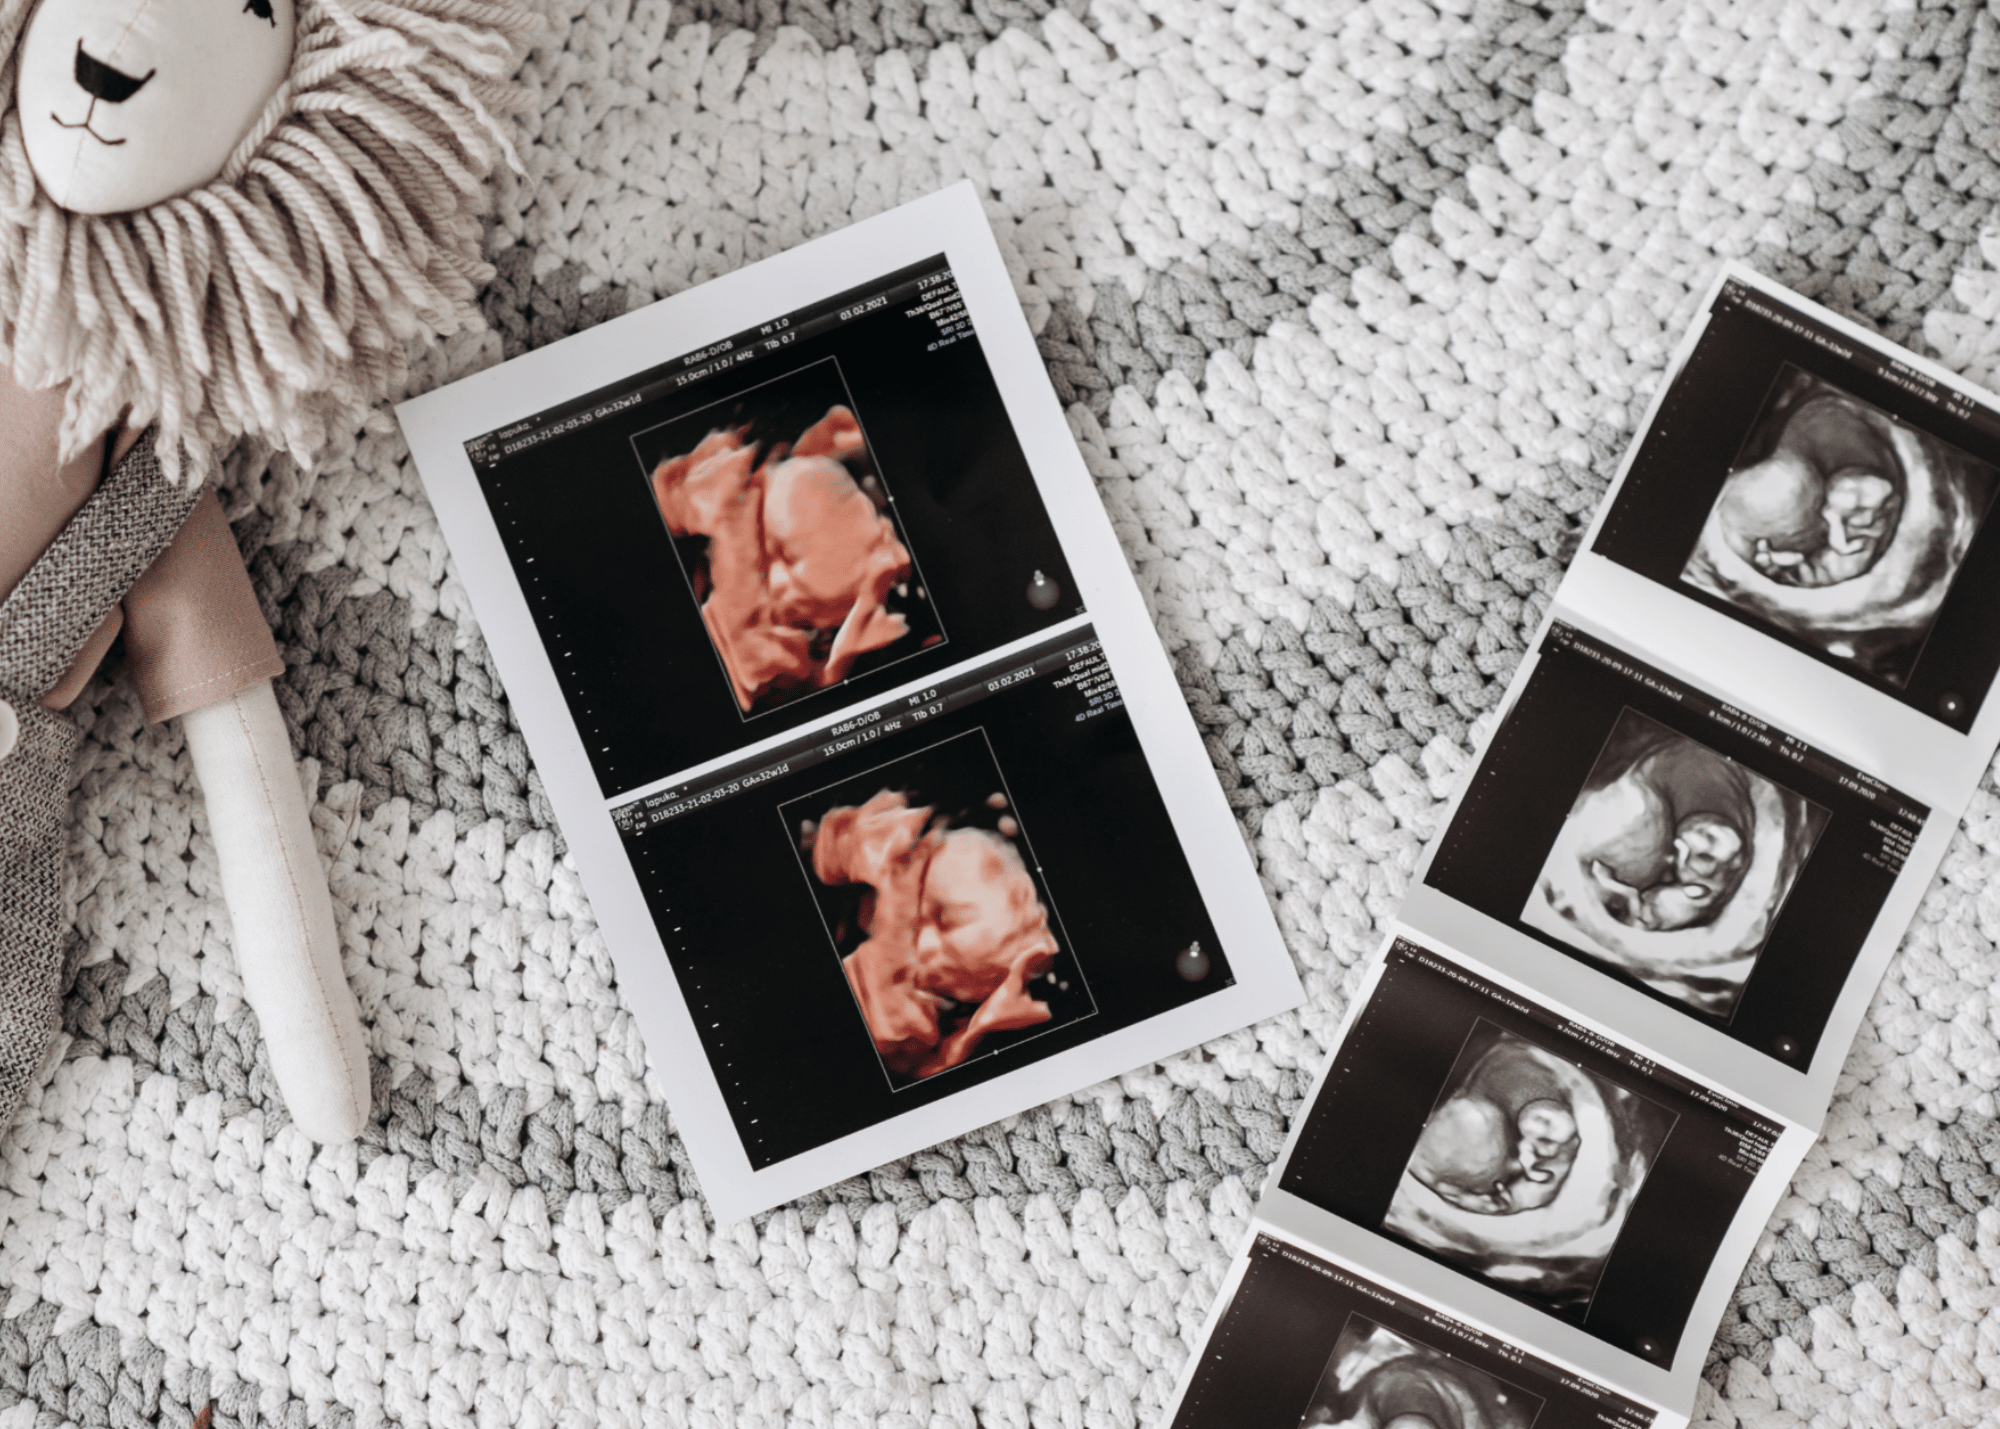

Du test de grossesse positif jusqu’au post partum:

Votre test de grossesse est positif ? Félicitations ! Et maintenant que se passe il? Qui appeler ? Découvrez toutes les réponses à vos questions grace à ce webinaire gratuit

Après un test de grossesse positif cela peut être un peu déroutant. Qui appeler ? Quel suivi effectuer ? Ou se trouvent les ressources dans ma région. Ce webinaire vous permettra d’avoir une boussole pour votre début de grossesse et d’aller frapper aux bonnes portes après avoir obtenu un test de grossesse postif. Début de grossesse, suivi de grossesse et support pour le post partum y sont abordés.